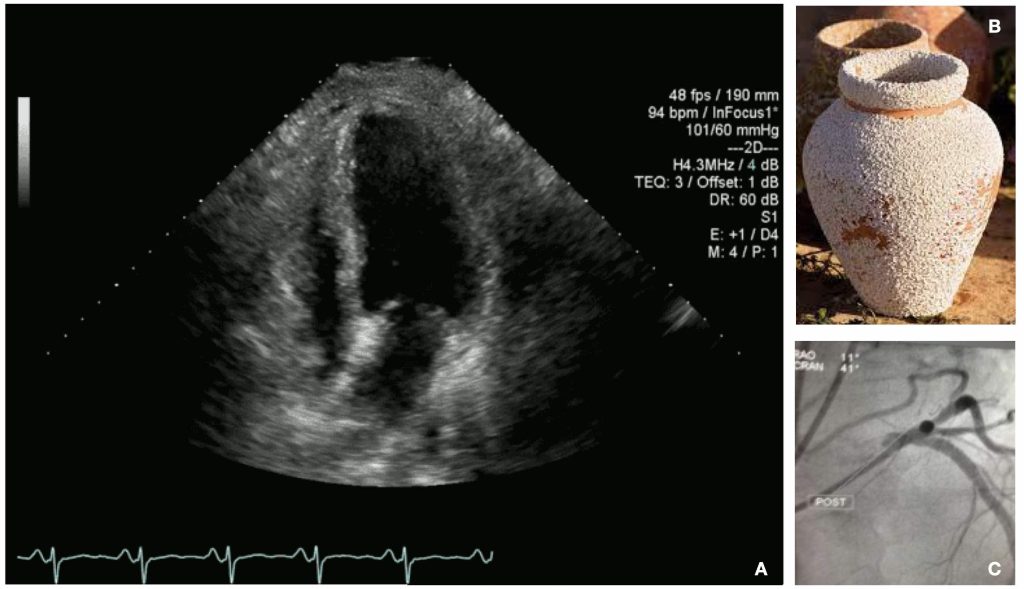

It’s difficult to differentiate Broken Heart Syndrome from a heart attack in the early stages of an occurrence. Symptoms and early test results from an EKG and cardiac blood markers will appear similar. Brenda’s echo and imaging test results, however, proved telling. Echocardiogram captured the ballooning shape of her left ventricle (LV), and the imaging test showed no blockage, the tell-tale sign of a heart attack.

Broken Heart Syndrome (stress-induced cardiomyopathy, takotsubo cardiomyopathy (TCM), or apical ballooning syndrome) is a usually short-term heart condition. It occurs as a result of severe emotional or physical stress and mimics the symptoms of a heart attack. The condition also presents as a transient regional systolic and diastolic dysfunction of the LV. This means that a part of the heart, usually the inferior end (apex), enlarges, causing the left ventricle to increase in size. Likewise, this impedes the heart’s ability to pump blood.

Unlike a heart attack, Broken Heart Syndrome can occur in the absence of obstructive coronary artery disease or acute plaque rupture. Unlike the heart arteries of heart attack patients, the arteries of Broken Heart Syndrome patients remain unblocked. In Brenda’s case, even though blood flow in the heart’s arteries decreases. In most cases (75-80%), the wall motion abnormality resembles an octopus trapping pot (from the Japanese word takotsubo). These pots have a narrow neck and rounded lower area that takes on an apical ballooning form.

As doctors examined Brenda in ED, they, indeed, found that her LV took on this shape while the rest of her heart continued to work properly, even if it contracted more forcefully. However, in cases where a midventricular ballooning form takes shape, in which the mid-LV is hypo- or akinetic, and normal apical and basal contraction occurs (10-20% of patients), there’s a more severe reduction in cardiac output and an occurrence of cardiogenic shock.